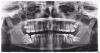

feniks Опубликовано 14 июля, 2011 Поделиться Опубликовано 14 июля, 2011 Здравствуйте! Помогите пожалуйста! У меня не правильно расположены зубы мудрости.(все четыре). На нижней челюсти 7 зуб лежит под восьмым. Что делать? Я обращалась к хирургам, они говорят, что надо удалять. Но я боюсь. Сказали, что 7 зуб лежит в челюстном канале, где проходят лицевые нервы. Если их заденут, то может он онеметь половина лица. Я хотела узнать, можно ли такие зубы выправить ортодонтически? Можно ли их выправить с помощью брекетов? На сколько это рискованно? Мне говорят что это опасно, что может произойти вывих зубов?. Посоветуйте пожалуйста, что мне делать? К кому обратится? За ранее всем спасибо. Ссылка на комментарий

Большой Зеленый Опубликовано 14 июля, 2011 Поделиться Опубликовано 14 июля, 2011 (изменено) Здравствуйте! Помогите пожалуйста! У меня не правильно расположены зубы мудрости.(все четыре). На нижней челюсти 7 зуб лежит под восьмым. Что делать? Я обращалась к хирургам, они говорят, что надо удалять. Но я боюсь. Сказали, что 7 зуб лежит в челюстном канале, где проходят лицевые нервы. Если их заденут, то может он онеметь половина лица. Я хотела узнать, можно ли такие зубы выправить ортодонтически? Можно ли их выправить с помощью брекетов? На сколько это рискованно? Мне говорят что это опасно, что может произойти вывих зубов?. Посоветуйте пожалуйста, что мне делать? К кому обратится? За ранее всем спасибо. Да восьмерки веселенькие.Всё удалять и 47 тоже .Для опытного хирурга это совсем не проблема. Нерв называется нижний альвеолярный .Это веточка тройничного нерва , лицевой нерв здесь не причем .Это другой нерв. По этому снимку сказать что 100% зуб у нерва нельзя .Чаще всего нерв в этом месте проходит гораздо язычнее т.е. в стороне от зуба .Этот снимок двухмерный .Точно можно сказать только по КТ .НЕ бойтесь .просто доверьтесь доктору... Изменено 14 июля, 2011 пользователем Большой Зеленый Ссылка на комментарий